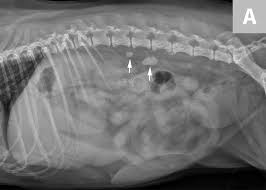

New Alternatives For Minimally Invasive Management Of Uroliths Ureteroliths Vetfolio

New Alternatives For Minimally Invasive Management Of Uroliths Ureteroliths Vetfolio from d36ai2hkxl16us.cloudfront.net

Get regular urine tests to confirm healthy kidneys. Just having kidney stones may not cause any symptoms, but when they begin to move or pass into your ureter (ureteral stones), you will likely experience symptoms. Kidney stone disease, also known as nephrolithiasis or urolithiasis, is when a solid piece of material (kidney stone) develops in the urinary tract. Some stones are tiny and pass through without causing symptoms. Most kidney stones eventually pass from the kidney through the ureter and bladder and finally through the urethra on their own. Kidney stones are small pieces of hard, crystallized material that form in the kidney. Some kidney stones manage to travel into the ureter. Phillips, a blocked ureter can be a common problem in cats.

Treatment of kidney stones in cats a reason to treat kidney stones is bacterial urinary infections that recur or cannot be cleared.